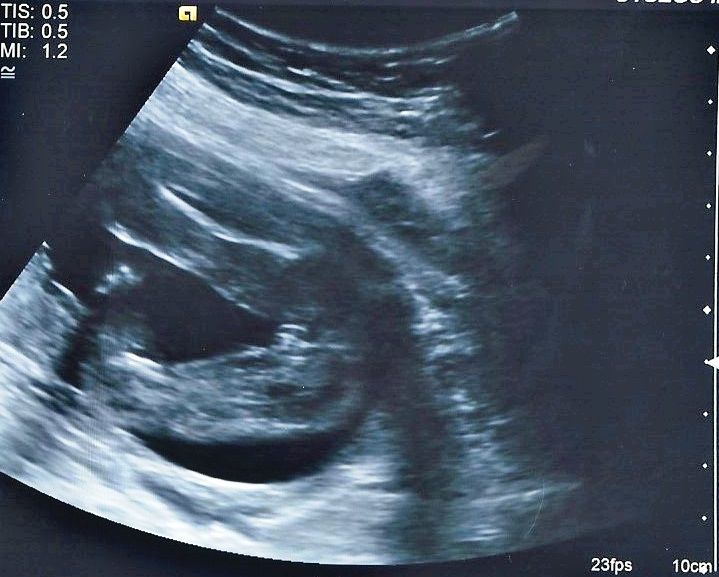

Attachment 23347

P.s that fork you see on the last image is not the nub. Its distortion from movement. This was for all you skull guessers. Classic girly skull